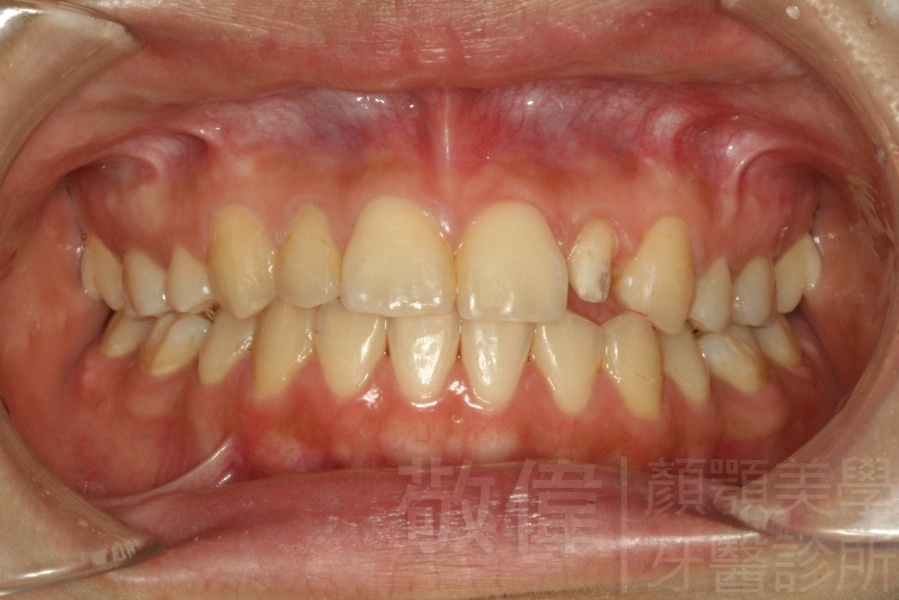

| 6 | 前牙美容 | 矯正+牙齦增補+晶鑽全瓷冠 | ||